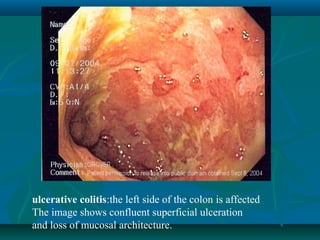

ulcerative colitis:the left side of the colon is affected

The image shows confluent superficial ulceration

and loss of mucosal architecture.